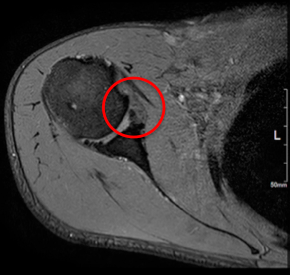

画像所見

| 術前:前方関節唇損傷あり | 術後6ヶ月 |

2016年4月にソフトテニス中に右肩関節を外転外旋位でボールを打ち返した際に脱臼感があり、自己整復をした上で、佐久平整形外科クリニックを受診されました。右肩関節唇損傷の疑いと診断し約3ヶ月間リハビリテーションを行いました。しかし、症状改善がなく造影MRI検査を施行し、結果より前方関節唇損傷と骨性Bankart病変と診断されました。ソフトテニスでのサーブ・スマッシュ時の疼痛・脱臼感などの症状が改善されず、今後も競技を続けるために手術を決められました。

現病歴:ソフトテニス中に右肩関節を外転外旋位でボールを打ち返した歳に脱臼感が出現しました。佐久平整形外科クリニック受診し右肩関節唇損傷の疑いで3ヶ月間リハビリテーションを行いましたが、症状改善なく造影MRI検査施行し、結果より前方関節唇損傷・骨性Bankart病変と診断されました。疼痛・脱臼感などの症状改善がみられず競技継続を希望されたため、鏡視下肩関節唇形成術を施行し、その術中で遊離体を発見したため摘出術も施行しました。